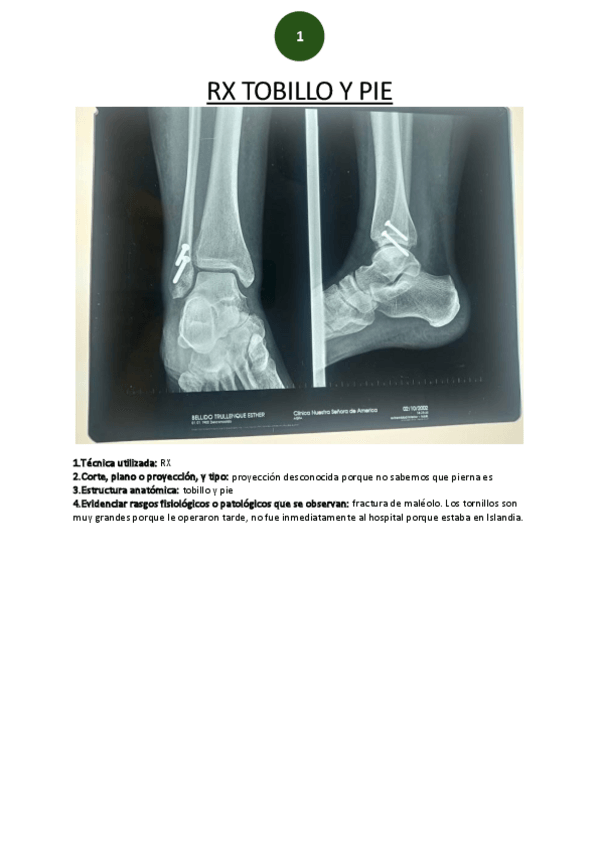

Prácticas - RX-tobillo-y-pie.pdf